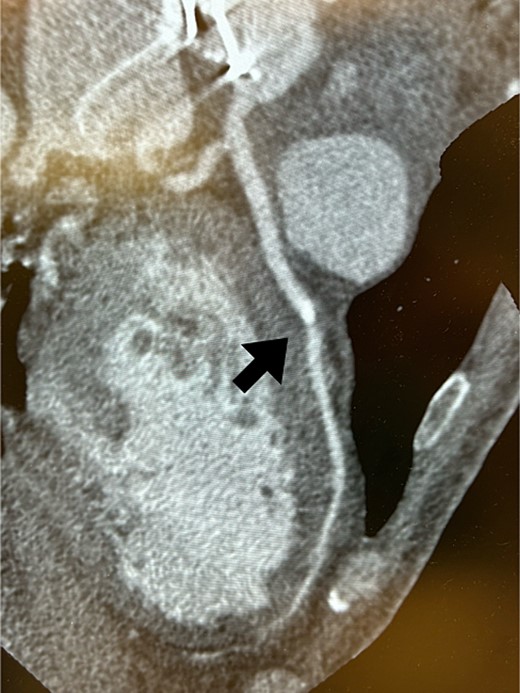

Postoperatively, an electrocardiogram revealed anterior ST-segment elevation, indicative of myocardial ischaemia. The patient then developed renal insufficiency. Given his haemodynamic stability, he was initially managed using coronary dilators and heparin. To improve renal function, coronary angiography was performed on the 10th postoperative day, which revealed a filling defect and 90% stenosis in the LAD artery (Fig. 1). Computed tomography (CT) revealed a high-density mass in the LAD artery with a mean CT value of 400 Hounsfield units (HUs) (Fig. 2). These findings indicated embolism, possibly due to a pledget from a previous surgery. A transcatheter approach was employed to remove the embolus, which was successfully extracted using a snare (Fig. 3a). Angiographic assessment revealed that the previously stenotic LAD demonstrated full perfusion, consistent with a thrombolysis in myocardial infarction (TIMI) flow grade of 3 (Fig. 3b). The patient recovered from catheterization without complications.

Coronary CT scans revealed a high-density area (arrow) in the LAD artery.